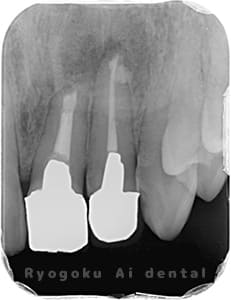

歯根端切除術の症例

Case01

- 原因

- 慢性根尖性歯周炎

- 治療期間

- 1回(消毒・洗浄も含めると3回)

- 治療内容

- 歯根端切除術

- 治療費用

- ¥110,000

他院で抜歯と判断され、インプラント治療を提案された患者様です。被せ物を外さずに、歯の根尖部に外科的にアプローチし、病気の部分を除去しました。

<リスク・副作用>

外科手術のため、術後に出血、痛みや腫れ、違和感を伴います。口腔内の状態によっては適応できないことがあります。歯根端切除で治らなければ抜歯を検討しなくていけない場合もあります。